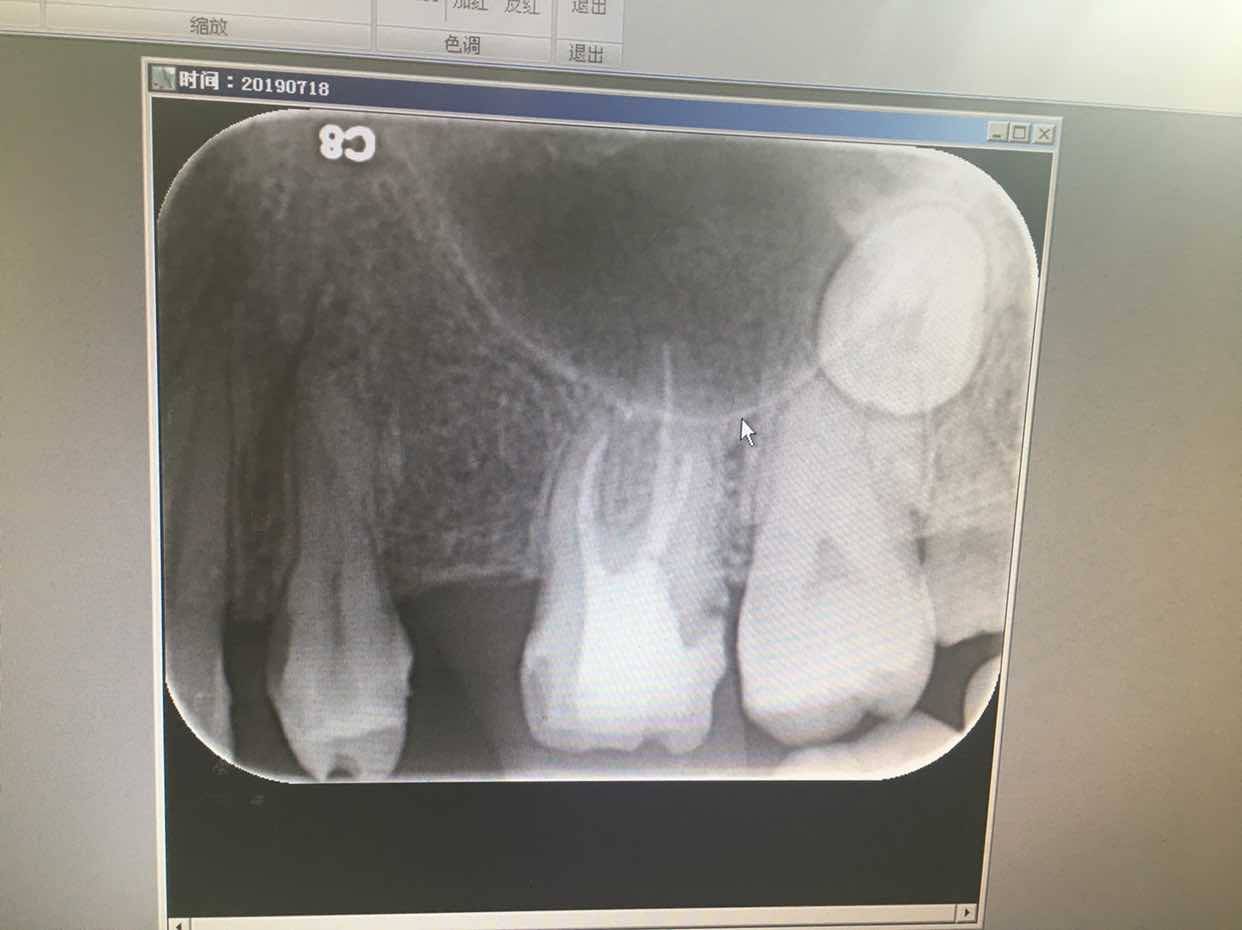

3、5月份根管治疗的牙齿咬物疼,复查时又拍片看了一下,大夫说看片子没问题,让再观察几个月